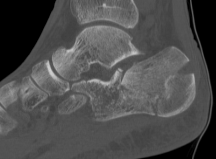

Non Operative Management

Indications

Sander I - non displaced

Sanders IV

Diabetes / smoker / peripheral vascular disease

Complications

Subtalar OA

Calcaneocuboid arthritis

Hindfoot varus malunion

Peroneal impingement or subluxation

Posterior tibial nerve entrapment

Difficulty with shoe wear